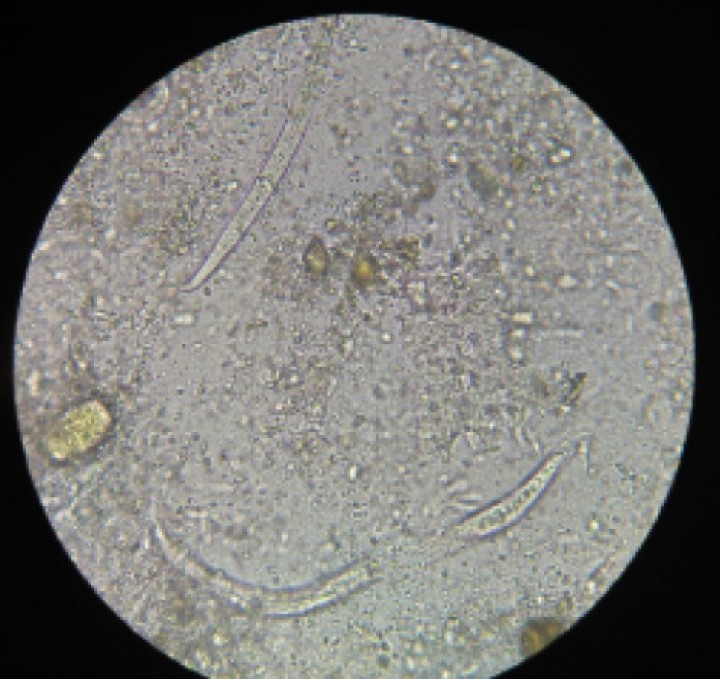

<p>Frotis fecal en el que se observan dos larvas de <em>Aelurostrongylus asbtrusus</em>. Aumentos totales x10.</p>

Figura 3

Frotis fecal en el que se observan dos larvas de Aelurostrongylus asbtrusus. Aumentos totales x10.

La evaluación citológica reveló una alta celularidad: innumerables macrófagos, neutrófilos y eosinófilos, grupos de células endoteliales respiratorias y larvas en varios campos del frotis (Fig. 2). Estos hallazgos fueron consistentes con inflamación piogranulomatosa a eosinofílica secundaria a la presencia de larvas de Aelurostrongylus abstrusus. En el cultivo de las muestras se aisló Bordetella bronchiseptica, y la prueba PCR para Mycoplasma spp. resultó negativa. La prueba de Baermann en heces reveló la presencia de Aelurostrongylus abstrusus (Fig. 3), lo que confirmó el diagnóstico de aelurostrongilosis.

La detección de las larvas en las citologías del lavado o los hisopos traqueales forma parte del protocolo diagnóstico, aunque la detección fecal mediante la técnica de Baermann se considera el método más sensible para la detección de larvas.[ Conboy, G: Helminth parasites of the canine and feline respiratory tract. Vet Clin Small Anim. 2009; 39: 1109-1126. [PubMed] ]